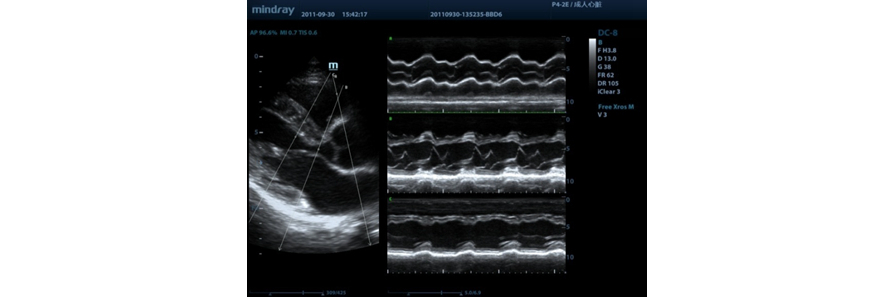

anatomiczny tryb M

Funkcja ta daje mo?liwo?? precyzyjnej obserwacji cz??ci anatomicznej poprzez swobodne umieszczanie linii trybu M pod dowolnym k?tem. Mo?na uzyska? lepsze obrazy dzi?ki jednoczesnemu wy?wietlaniu maksymalnie trzech linii trybu M.

Funkcja anatomicznego trybu M z dopplerem tkankowym

S?u?y do dok?adnej oceny ruchu mi??nia sercowego w ró?nych fazach, przy jednoczesnym okre?laniu synchronizacji mi??nia sercowego. Wysoka cz?stotliwo?? od?wie?ania zapewni Państwu dok?adne wyniki.